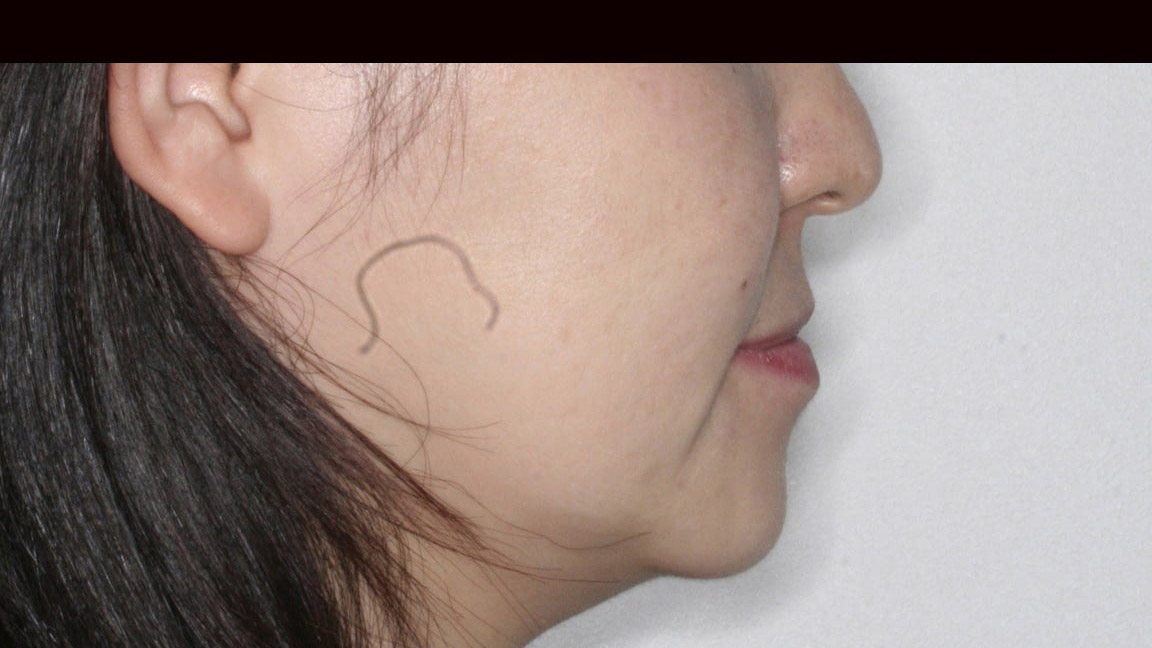

case-33 八重歯が気になる

| 年齢層 | 20代 |

|---|---|

| 性別 | 女性 |

| 主訴 | 【主訴】八重歯 【診断・症状】低位唇側転位 |

| 治療費用 | 検査・診断:税込38,500円/裏側矯正治療(リンガル矯正):税込1,397,000 |

| 治療期間 | 1年(19回) |

| 抜歯 | 有(上右5, 下右5) |

| 矯正の装置 | 裏側矯正(舌側矯正) |

| 副作用・リスク | 歯肉退縮,歯根吸収,疼痛,咬合の違和感,装置の違和感,虫歯,歯肉炎 |

Before